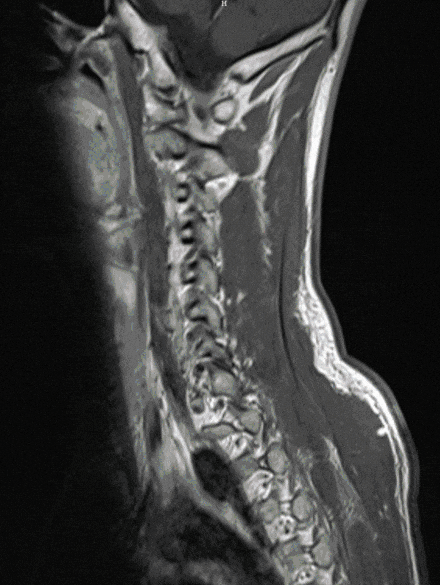

Neurinomas and neurofibromas are relatively common tumors that can lead to massive compression of the spinal cord from the outside. Not infrequently, these tumors occur in the context of hereditary diseases (neurofibromatosis). They threaten the function of the spinal cord and lead to the occurrence of pain or neurological deficits.